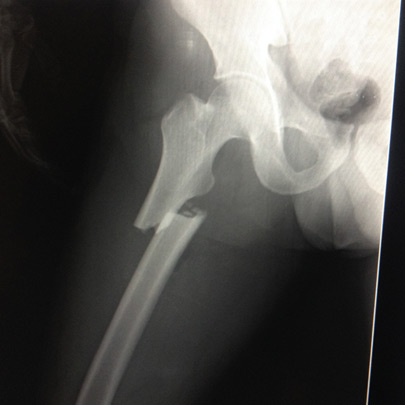

Fracturas y luxaciones

Prótesis